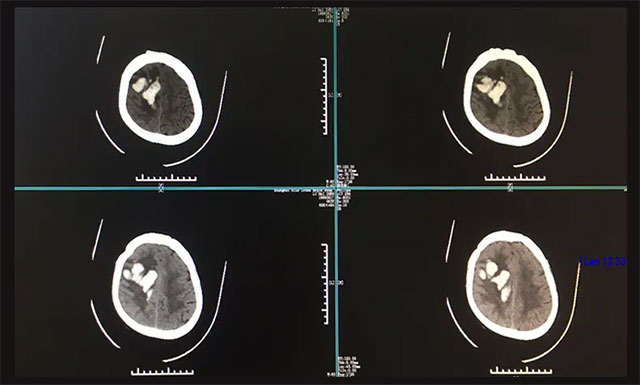

随后,曹先生紧急拨打120电话急救,遂将患者送至当地浙江省某医院进行救治,在该院紧急行头部CT检查,影像提示:患者右侧颞顶叶脑出血,两侧侧脑室后角少量积血。鉴于患者当时出血量很大,约为50ml,病情又比较严重,生命危急,应及早手术,但因各方面条件所限,该医院当时予以保守治疗,并建议患者家属转院。

入院后,完善其各项检查,为了进一步确定患者目前出血的具体情况,进行了头部CT检查,根据影像检查结果,与之前在他院CT结果相比,血肿量较前增多,右侧额颞顶叶出血灶(偏急性期)。经过会诊,潘仁龙主任和吴治群博士一致认为患者脑出血严重,处于昏迷,左侧肢体偏瘫,病情危急,需及早手术清除颅内血肿,否则生命会有危险。